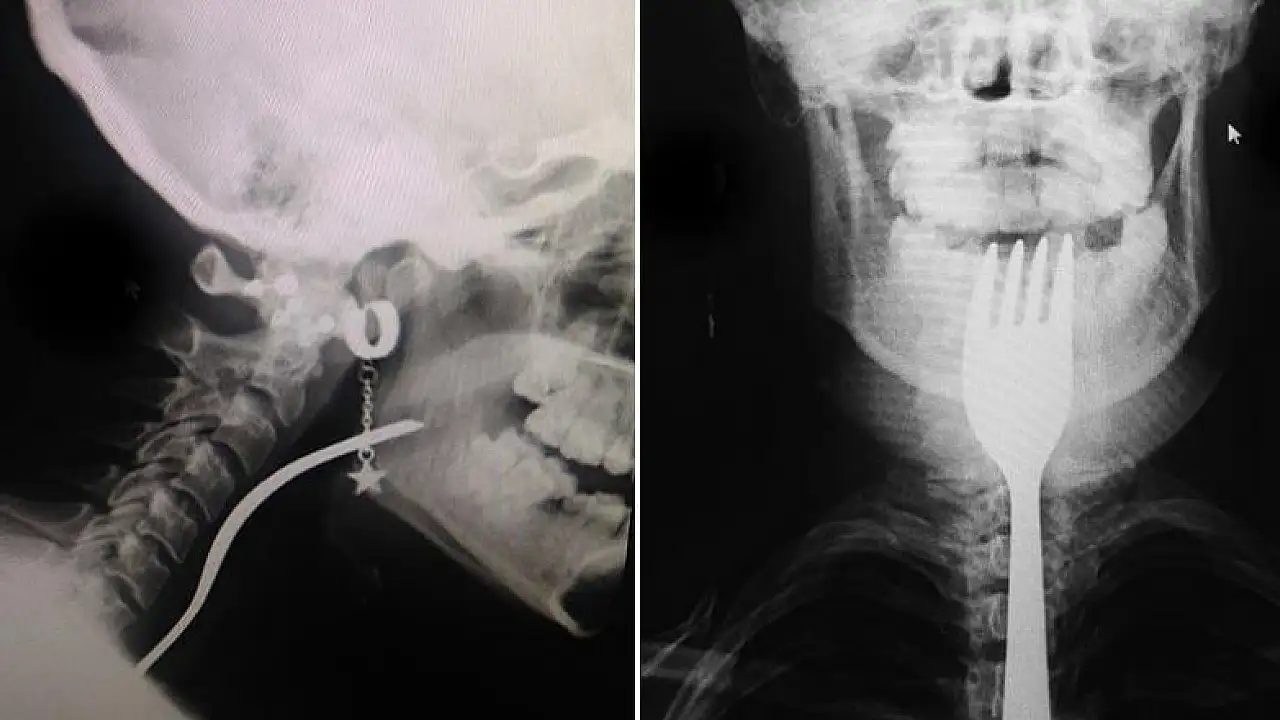

• Dişini karıştırdığı çatal boğazına takıldı

Dişini karıştırdığı çatal boğazına takıldı

Bursa'nın Orhangazi ilçesinde dişini karıştırdığı çatal boğazına girip takılan genç kız, hastaneye kaldırıldı.

Alınan bilgiye göre, Üreğil Mahallesi'nde ailesiyle yaşayan 19 yaşındaki N.A, çatalın ters bölümüyle dişini karıştırmaya başladı. Bu sırada genç kızın boğazına çatal girdi.

Taksici babası İ.H.A. tarafından Orhangazi Devlet Hastanesine kaldırılan N.A, ilk müdahalenin ardından Uludağ Üniversitesi Tıp Fakültesi Hastanesine sevk edildi.

Burada yapılan müdahale sonucu genç kızın boğazına takılan çatal çıkarıldı.